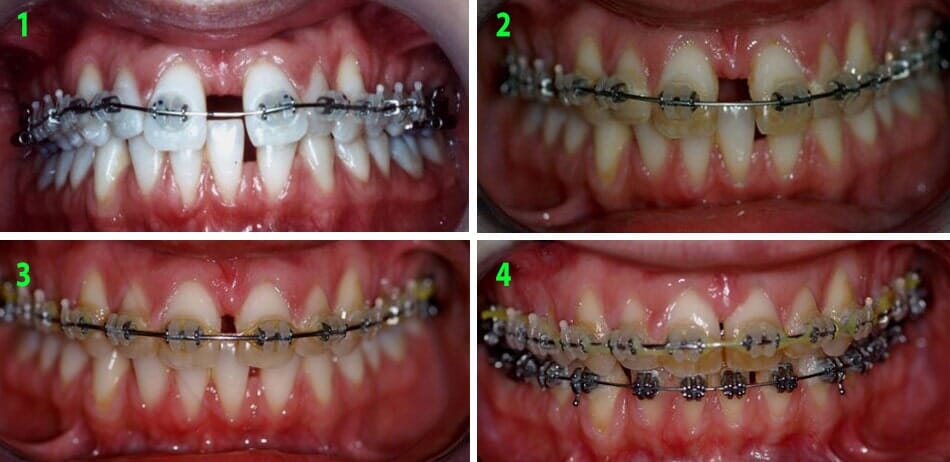

תמונות בתוך הפה

אחרי

תמונות מתוך הפה, אחרי

לפני

תמונות מתוך הפה, לפני

3. התאמת קשתות השיניים המסודרות זו לזו- מבוצעת לרוב ע"י גומיות בין לסתיות שהמטופל שם ומחליף בעצמו.

4. סיום המקרה- הבאת השיניים על פי הצורך לעמדותיהן האופטימליות.